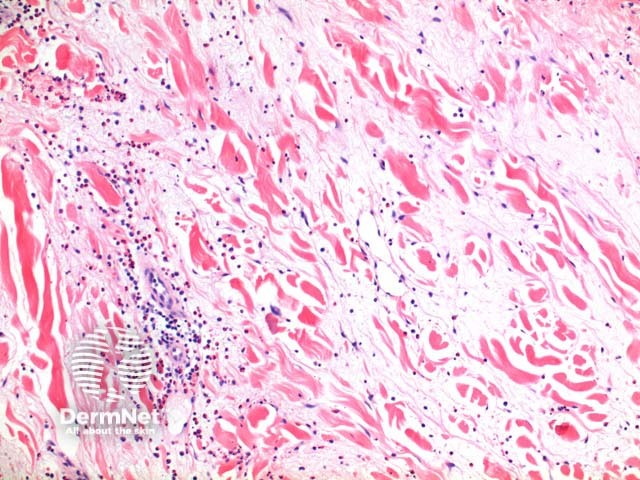

Scanning power view of Wells syndrome reveals a superficial and deep perivascular and interstitial inflammatory pattern (Figures 1 and 2). This can be seen to extend into the subcutaneous tissue (Figure 3) or even the underlying muscle. The inflammatory infiltrate is comprised of lymphocytes, histiocytes and abundant eosinophils (Figures 4,5 and 6). Degranulation of the eosinophils is seen forming flame figures (Figures 4 and 5). In this particular case extensive interstitial mucin is seen (Figures 4 and 5).

Figure 3